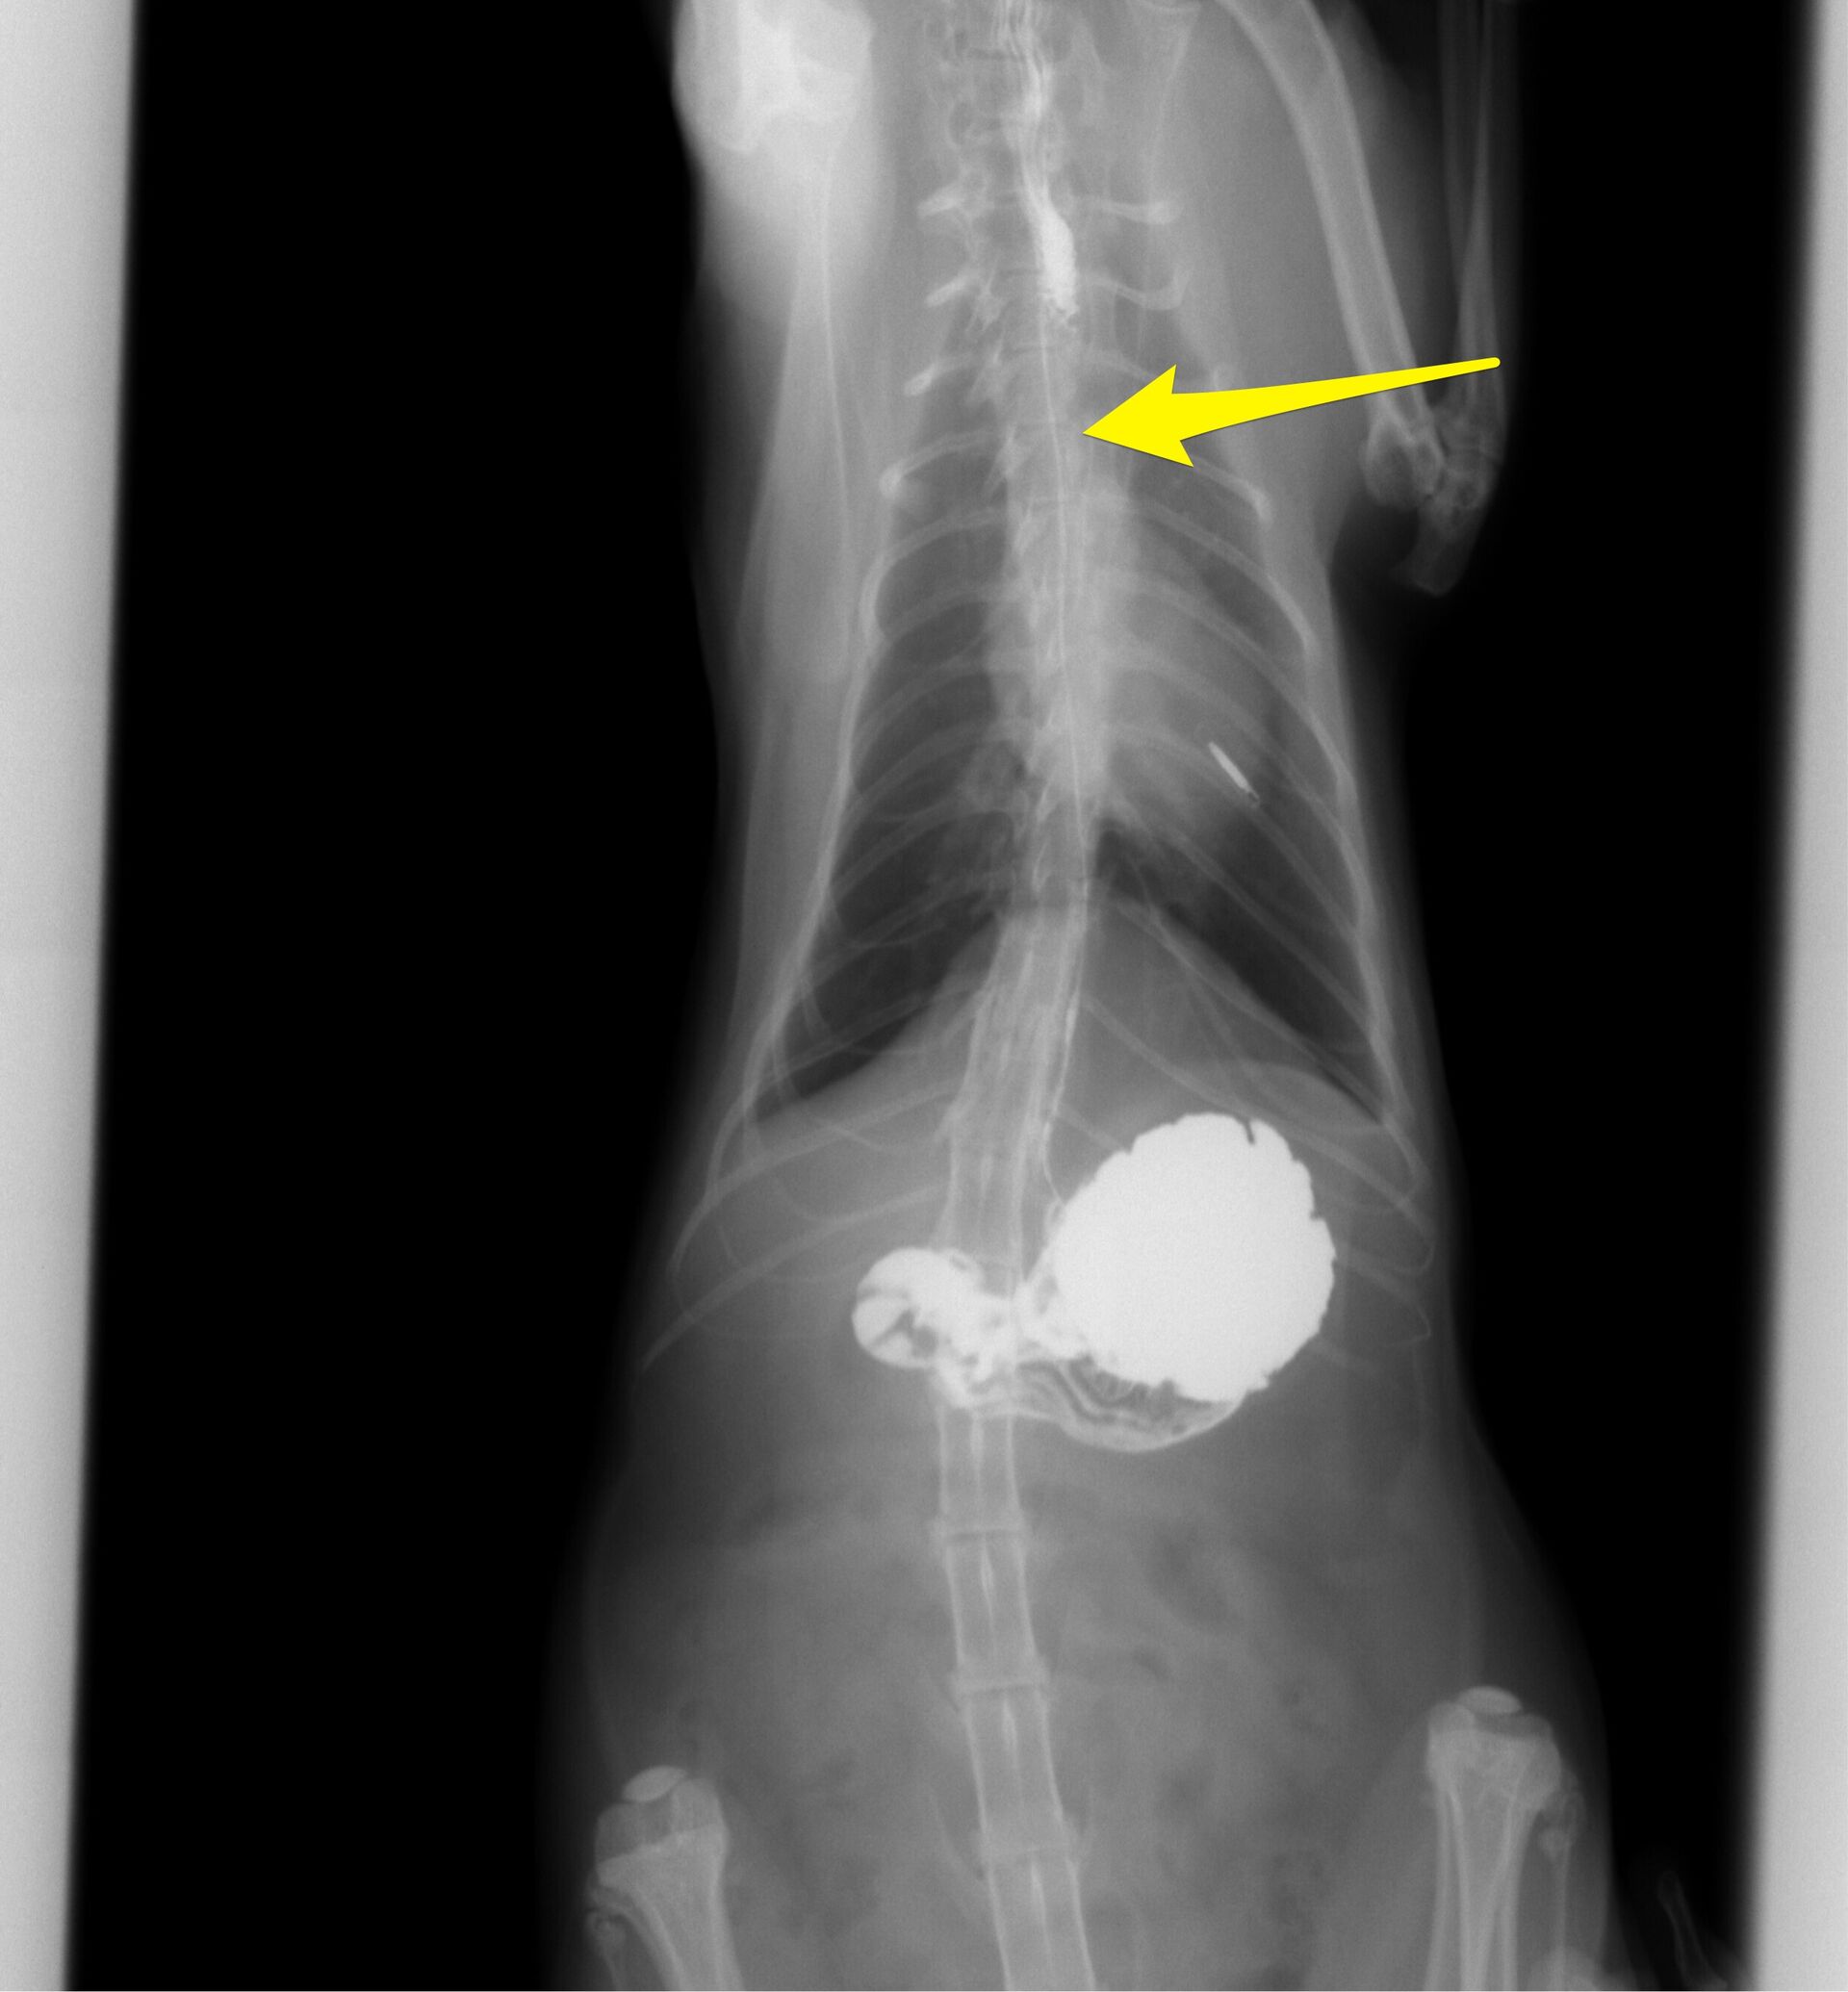

バリウムを飲ませた直後の写真ですが、矢印で示していますように食道にバリウムが残っています。これは紐状異物が食道にあることを示しています。その後4時間まで撮影しました。その結果が下の写真です。小腸まで達したバリウムは小腸の変形を示しています。これは紐状異物が小腸まで達していることを示しています。

こうなってしまうと、開腹して腸を切開し紐を切断しながら取り除くしかありません。実際、診察のその日の夜に緊急手術することになりました。その様子が下の写真です。